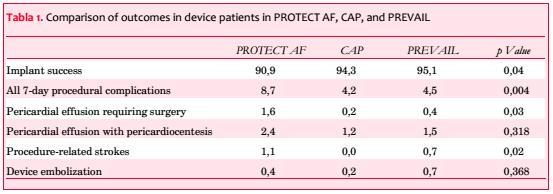

Posteriormente y en base a los resultados de eficacia de Protect AF se realizó el ensayo PREVAIL (Prospective Randomised Evaluation of the Watchman LAA Closure Device in Patients With Atrial Fibrilation vs Long Term Warfarin Therapy)(20). Se incluyeron 407 pacientes con una relación 2/1 de Watchman vs warfarina. Los resultados fueron publicados recientemente y se muestran en la tabla 1.

Superada la curva de aprendizaje se redujeron las complicaciones. La tasa de implante exitoso pasó de 90,3% a 95,0% con una significativa reducción del tiempo de procedimiento.